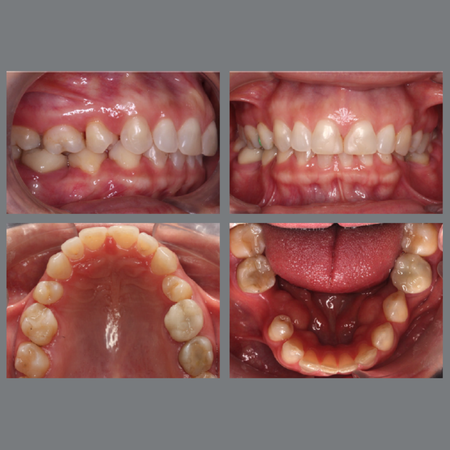

Facial profile attractiveness in orthodontically treated Class III malocclusion patients: a comparison of extraction and non-extraction protocols

Introduction: The treatment of Class III malocclusion has an important impact on facial and smile esthetics. Objective: To compare the facial profile attractiveness (FPA) of Class III malocclusion patients treated with and without premol...

Esthetics Angle Class III Soft-tissue profile